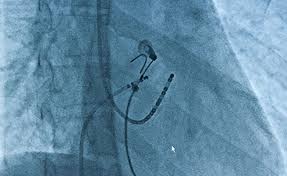

Ist die vorliegende Herzrhythmusstörung bereits bekannt kann bereits nach wenigen Minuten mit einer Ablation begonnen werden. Die Ablation wird mit einem speziellen Katheter durchgeführt häufig nachdem i. Die Elektrophysiologische Untersuchung EPU ist eine besondere Form der Herzkatheter-Untersuchung mit der Herzrhythmusstörungen detailliert analysiert werden können.

Den Möglichkeiten des Verfahrens stehen eine Reihe von relevanten Limitationen entgegen. Die Katheterablation wird zumeist zusammen mit der elektrophysiologischen Untersuchung durchgeführt die zunächst zur Klärung des Mechanismus Auffinden der verantwortlichen Zellen dient. Elektrophysiologische Untersuchung EPU Aufgrund Ihrer Herzrhythmusstörung ist zur weiteren Therapie und Risikoabschätzung eine Elektrophysiologische Untersuchung EPU notwendig über die wir Sie zunächst informieren möchten. Die elektrophysiologische Untersuchung mit gleichzeitiger Ablation kann zeitaufwendig sein. Oft ist eine sofortige Behandlung während der Herzkatheteruntersuchung möglich Ablationsbehandlung. Mit einer elektrophysiologischen Untersuchung EPU wird zunächst festgelegt wo genau im Erregungsleitungssystem die Ablation stattfinden soll. Bei Ihnen wurde eine elektrophysiologische Untersuchung mit Ablation vorgenommen. Die Ablation wird mit einem speziellen Katheter durchgeführt häufig nachdem i. Dabei soll vorerst durch die elektrophysiologische Untersuchung entschieden werden um welche Art von Herzrhyth-musstörungen es sich handelt und welche Behandlungsmöglichkeit sich in Ihrem Fall empfiehlt.